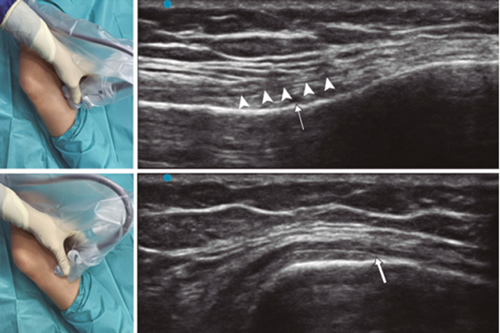

Fig. 3. Sonoanatomy and technique for performing superior medial genicular nerve block (SMGN). The transducer is located on the distal long axis of the femur and once the position of the SMGN (asterisks) is known, the probe is rotated 90 degrees to obtain a view of the femur short-axis (don't forget to keep the same depth that we find the SMGN on the long axis). VM (vastus medialis).

Fig. 4. Sonoanatomy and technique for performing inferior medial genicular nerve block (IMGN). The transducer is located on the proximal long axis of the tibia and we identify the vasculonervious package of the IMGN (arrow) just below medial collateral ligament (arrowheads). Then the probe is rotated 90 degrees to obtain a short-axis view of the tibia (don't forget to keep the same depth as the IMGN found on the long axis).

After performing knee asepsis/antisepsis, surgical field placement, and the sterile sheath of the high frequency linear transducer, we proceed to locate the SMGN (Figure 3). Placing the probe in a coronal plane on the inner face of the knee, we slide it cranially to visualize the junction of the metaphysis to the femoral diaphysis and the superior medial genicular artery/nerve (ASMGN), usually located near the periostium of the femur (if this neurovascular structure is not found, the junction between metaphysis and femoral diaphysis is taken as a reference). The mid-point of the transducer corresponding to ASMGN is then marked on the skin and the transducer is rotated to be placed in the transverse or axial plane to view ASMGN on the short axis (if this structure is not visible, confirm that we are at 50 % depth of the femur). In this cross-section the needle of the TRF is advanced in plane from anterior to posterior toward the ASMGN or to a depth of 50 % of the thickness of the femur. Finally, the transducer is rotated 90° again, leaving it in a coronal plane to check that the needle tip is near the ASMGN or the junction of the metaphysis and femoral diaphysis (14,16,19).

To locate the IMGN (Figure 4), we placed the transducer in a coronal plane on the inner face of the knee, sliding it caudally to identify the diaphysis junction with the tibial metaphysis and the inferomedial genicular artery/nerve (AIMGN). And we repeat the same steps we used for SMGN. If the AIMGN is not found, the reference to be taken shall be the depth of 50 % of the thickness of the tibia (14,16,19).